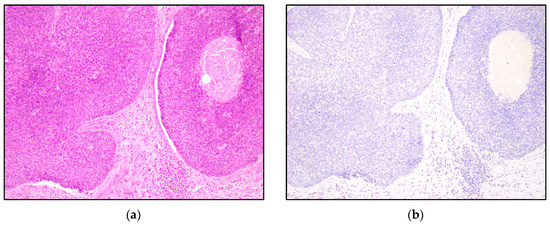

| TRPS1 Expression | Trichoblastoma N = 13 | Trichoepithelioma N = 15 | Basal Cell Carcinoma N = 15 |

| Negative n (%) | 7 (54%) | 6 (40%) | 10 (67%) |

| Low Positive n (%) | 1 (8%) | 6 (40%) | 5 (33%) |

| Intermediate Positive n (%) | 2 (15%) | 1 (7%) | 0 (0%) |

| High Positive n (%) | 3 (23%) | 2 (13%) | 0 (0%) |